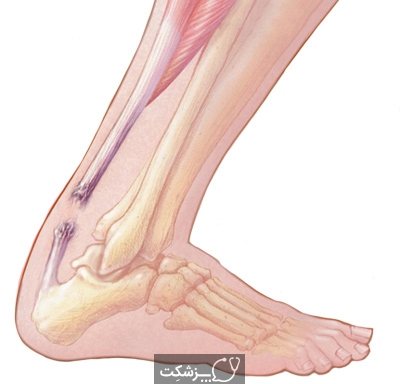

پارگی تاندون

- ممکن است هر دو تاندون چهار سر و تاندون پاتلار یا کشکک به طور جزئی یا کاملاً پاره شوند.

- پارگی تاندون چهار سر ران معمولاً در ورزشکاران بالاتر از 40 سال اتفاق می افتد.

- پارگی تاندون پاتلا به طور معمول در افراد جوانی که تاندونیت قبلی یا تزریق استروئیدی به زانو داشتند، رخ می دهد.

علائم پارگی تاندون

پارگی چهار سر ران یا تاندون پاتلار باعث درد می شود. آن دسته از افراد با پارگی کامل قادر به دراز کردن زانو نیستند.

درمان پارگی تاندون

- پارگی تاندون نیاز به مراقبت فوری دارد. آن ها معمولاً به ترمیم جراحی نیاز دارند،

- در حالی که پارگی جزئی ممکن است به تنهائی با اسپلینت درمان شود.